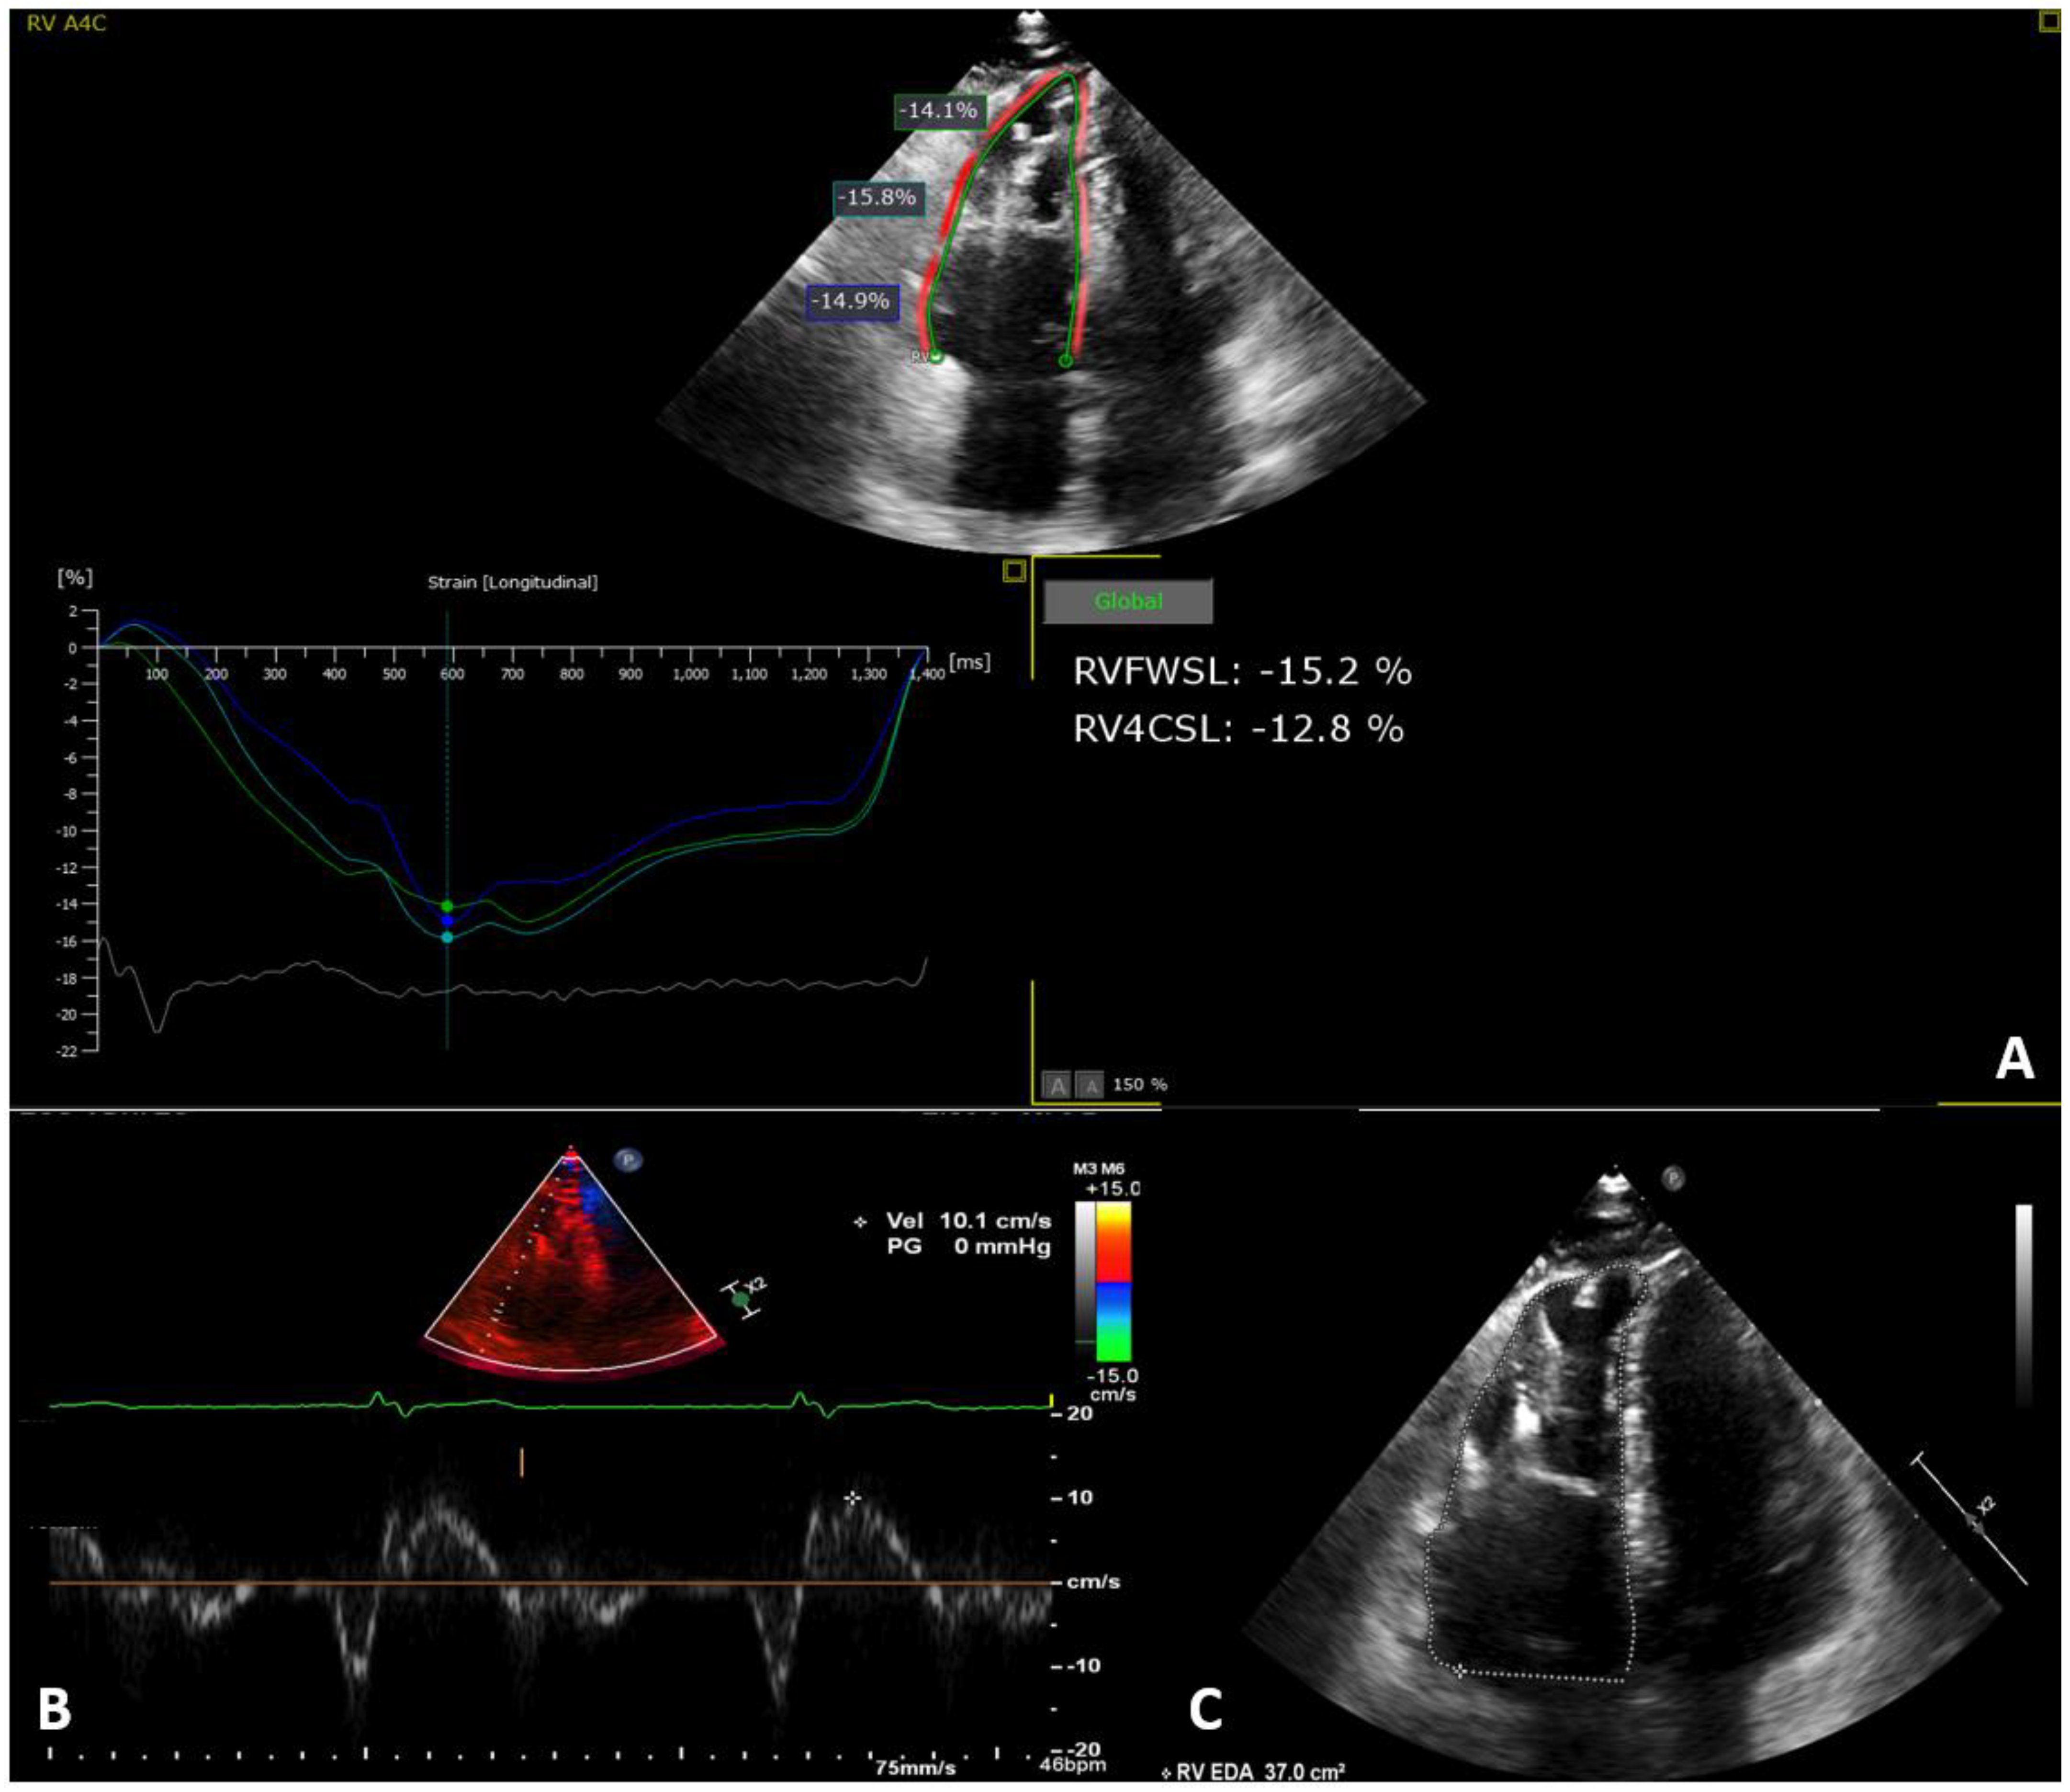

| 37.00 (33.75, 39.25) |

| 37.50 (34.75, 41.25) |

| 37.471 (35.75, 40.00) |